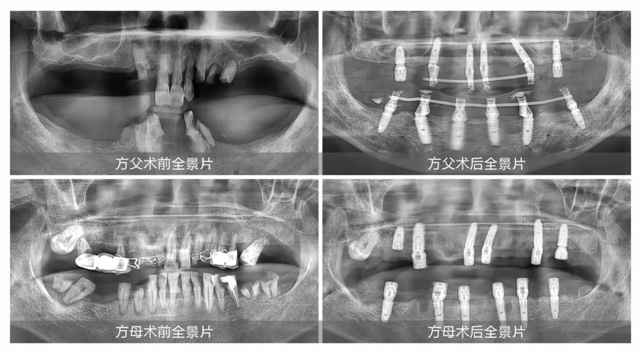

兒女們不怕出錢出力,兩老口也從善如流。2024年6月25日,方先生和弟弟,一人牽一個,陪伴父母在新橋口腔成功完成全口即刻種植。“缺牙問題不能將就,就算安假牙能省再多錢,吃東西不方便的話還是很惱火。”方先生說:“父母辛苦了一輩子,晚年安享口福是很重要的。”

幸福和美 愛在新橋

7月中旬,方先生帶父母回新橋口腔復查拆線,此時距離兩位老人種牙剛好半個月。方先生開心地告訴我們:“現在我父母食欲都不錯,胃口提升了很多,以前說話漏風,時不時還會流口水,種了牙以后就不存在了,人都顯得年輕了十歲。”